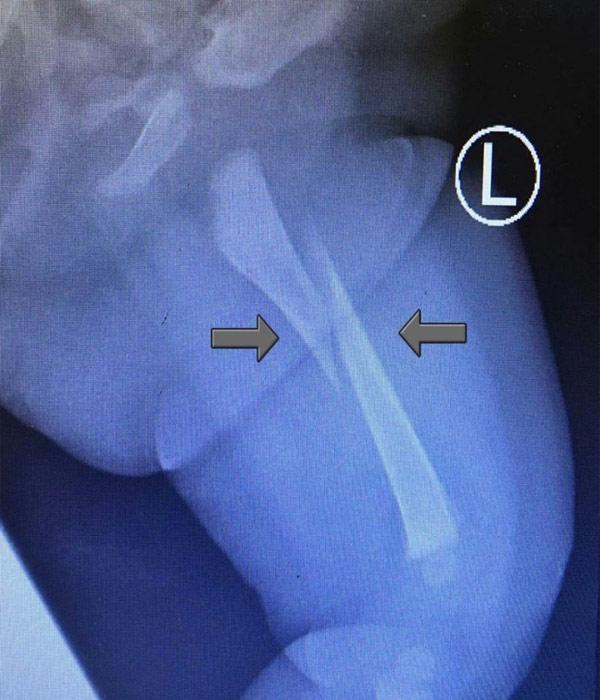

Kết quả chụp X-quang cho thấy phần xương đùi trái của bé gái bị gãy đôi. (Ảnh Worldofbuzz)

Lo lắng con bị bệnh, người cha lập tức đưa bé tới bệnh viện Shah Alam, Selangor để kiểm tra. Tại đây, sau khi tiến hành thăm khám và chụp chiếu các bác sĩ kết luận bé bị gãy xương đùi trái.